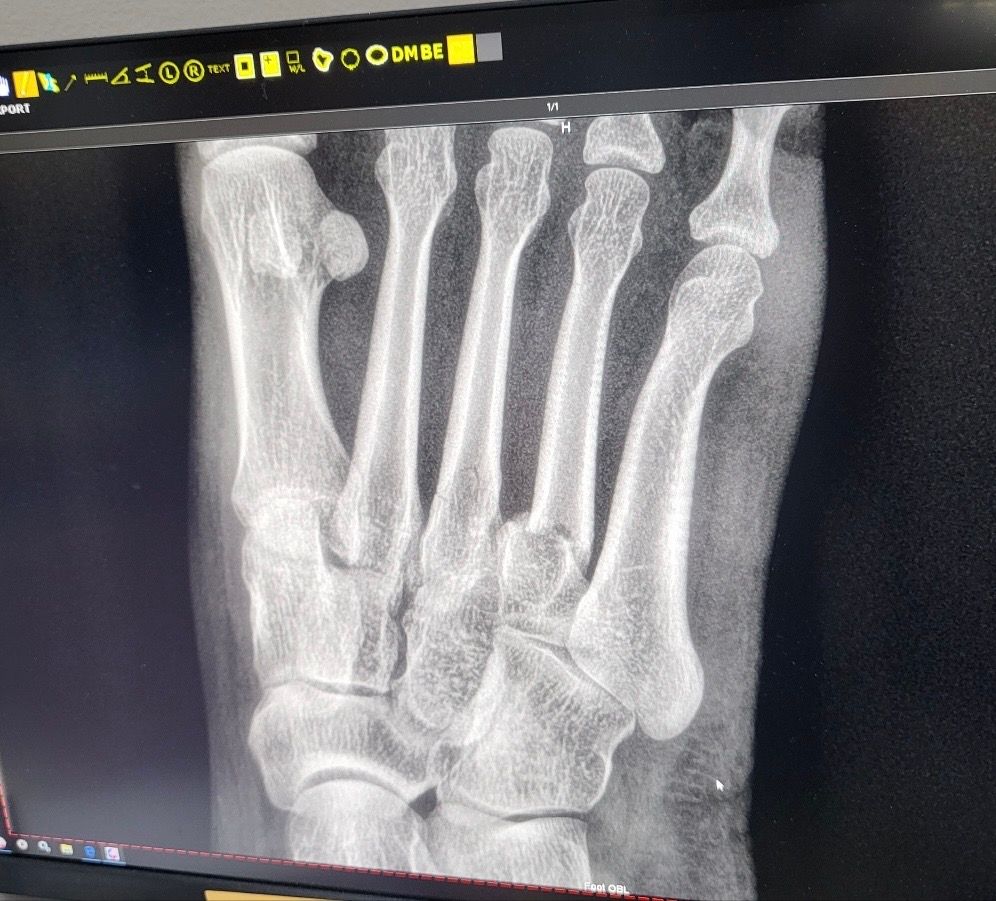

넘어져 발등이 심하게부어서 병원가니 뼈부러짐

어제밤 넘어져 발등이 심하게 멍들고 부어서 근처 한인병원에서 엑스레이를 찍었는데

3,4번 뼈가 부러진것같다고 합니다

4번째 뼈는 어긋난것같아보이는데 심각한가요

• 2번 째 사진

중족골이 어긋난 골절 소견으로 이런경우는 무조건 고정하는 splint / 반깁스라도 하셔야 합니다. 가급적 정형외과 병원에 찾아가서 진료 보시는게 좋겠습니다.

이야기 하신대로 4번뼈는 골절 후 틀어진 상태이기 때문에 빠른 수술이 필요합니다.

한달이나 기다리시면 틀어진 상태로 뼈가 굳기 때문에 그때 가서 수술을 하면 오히려 수술이 더 어려워집니다. 어떤 일정이신지 모르겠지만 가능하다면 일정을 당겨서 빠른 시일 이내에 수술받으시기 바랍니다.

반깁스를 해서 고정을 하고 체중부하는 절대 하시면 안되겠습니다. 목발 사용해주시기 바랍니다.